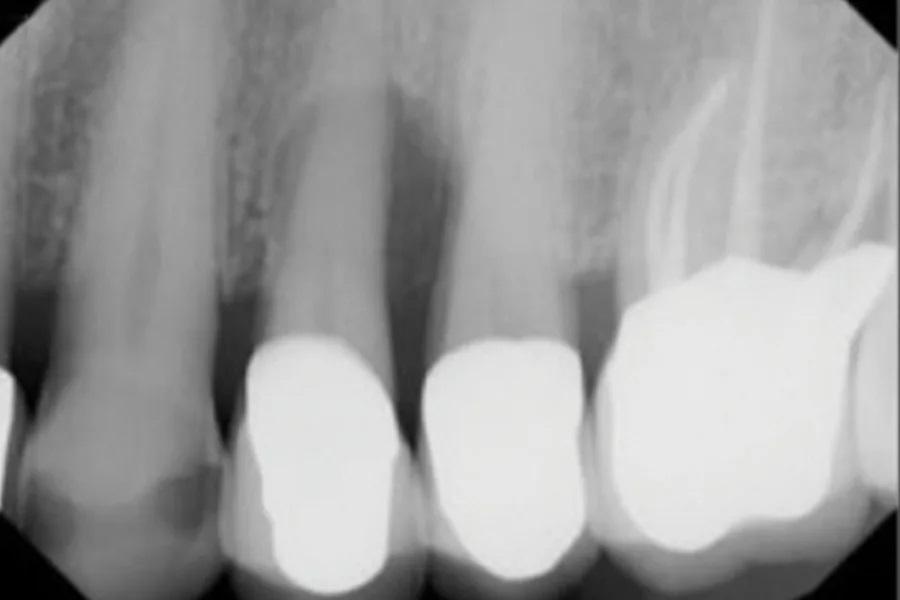

На контрольном осмотре через 16 месяцев клиническая оценка выявила сохраненный объем гребня и стабильную кератинизированную мягкую ткань (Фото 22 и Фото 23). Рентгенологический анализ подтвердил стабильный уровень кости вокруг имплантата № 2.4 и положительные рентгенологические изменения, свидетельствующие о регенерации тканей на медиальной поверхности зуба № 2.5, включая восстановление периодонтальной связки (Фото 24).

Фото 24. На контрольном осмотре через 16 месяцев: ПА рентгеновский снимок показывает стабильный уровень краевой кости, патологии не выявлено.